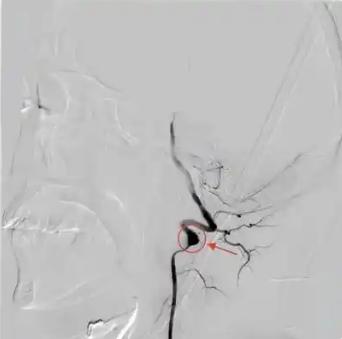

“悲剧还是发生了!”江苏南京,一28岁小伙打完篮球后,突然感觉右侧肢体无力,甚至连话都说不出来,送往医院检查后发现是“中风”,手术结束一个月后,小伙又去打篮球,结果再次引发“中风”,这次还留下了严重的后遗症!网友:非得一棵树吊死? 南京篮球场边,28 岁的于先生(化名)刚投进最后一个球,突然双腿一软栽倒在地。 右边身子完全动不了,想喊救命,嘴巴却发不出清晰的声音,只能含糊地哼哼 ,这是他两个月内,第二次中风了! 谁能想到,这个平时下班打球、周末跑步的阳光小伙,会被 “中风” 这个 “老年病” 缠上,还彻底毁了原本健康的人生。 第一次中风的场景,至今还让他的朋友心有余悸。 两个月前,一场普通的篮球赛结束后,于先生突然感觉右胳膊右腿发沉发软,像灌了铅一样抬不起来,嘴角也控制不住地往一边歪。 朋友见状不对,没敢耽误,赶紧把他送进了江苏省人民医院。 检查结果出来,所有人都倒吸一口凉气:他的左侧椎动脉 V3 段形成了夹层动脉瘤,基底动脉已经完全堵死。 医生说,再晚几分钟,脑干可能坏死,人都可能没了。 紧急手术后,堵塞的血管被打通,于先生恢复得不错,几周后就能下床活动。 他觉得自己年轻身体好,手术成功就没事了,压根没把医生 “别做剧烈运动” 的叮嘱放在心上。 出院才一个月,他就忍不住回到了心心念念的篮球场。 那天的比赛打得格外激烈,快速转身、后仰跳投,他像以前一样拼尽全力,完全忘了自己刚从鬼门关走了一遭。 可他不知道,自己的血管还处在脆弱期,这些猛动作,正在悄悄酝酿一场更可怕的悲剧。 第二次中风后,于先生被再次送进医院。 检查结果比上次更糟 —— 脑干出现了新的梗死灶。 医生拼尽全力抢救,保住了他的命,却没能留住他的健康。 现在的他,右侧肢体完全瘫痪,言语能力严重受损,从一个活力四射的青年,变成了生活无法自理的患者。 好好的小伙子,怎么会接连中风? 江苏省人民医院的神经内科专家黄琳道出了真相,这个诱因,很多爱运动的人都在犯! “剧烈运动时,头颈突然快速旋转、后仰,椎动脉就像一根软管子被硬拧,内膜很容易撕裂。” 血液会钻进撕裂的缝隙里,慢慢形成一个 “小泡”,也就是夹层动脉瘤。 一旦这个 “小泡” 堵了血管,或者破裂,就会引发中风。 更吓人的是,这种血管损伤早期几乎没什么症状。 年轻人总觉得 “身体好,扛得住”,继续高强度运动,血压一升高,血流紊乱,悲剧就来了。 网友看完这事儿,都吓出一身冷汗: “我天天打篮球,后仰跳投是家常便饭,现在想想太危险了!” “原来中风不是老人的专利,年轻人真不能瞎逞强!” 医生也提醒,不管年纪大小,都要记住中风的信号:嘴歪、言语不清、肢体无力、视物模糊。 只要出现其中一个,都得立刻就医,千万别耽误。 尤其是曾经得过动脉夹层或脑梗的人,更要听医生的话,别做剧烈运动、重体力活,也别大幅度扭脖子。 于先生的悲剧,真的太让人惋惜了。 运动本来是为了健康,可一旦超出身体承受范围,用错了方式,就变成了伤害自己的利器。 年轻从来不是 “无敌资本”,健康也不是用来挥霍的。 不管是打球、跑步,还是其他运动,都得循序渐进,讲究科学。 别为了一时尽兴,让一辈子都活在遗憾里。 你平时运动喜欢做猛动作吗?有没有遇到过身体突然不适的情况? 对此,你有什么看法呢?